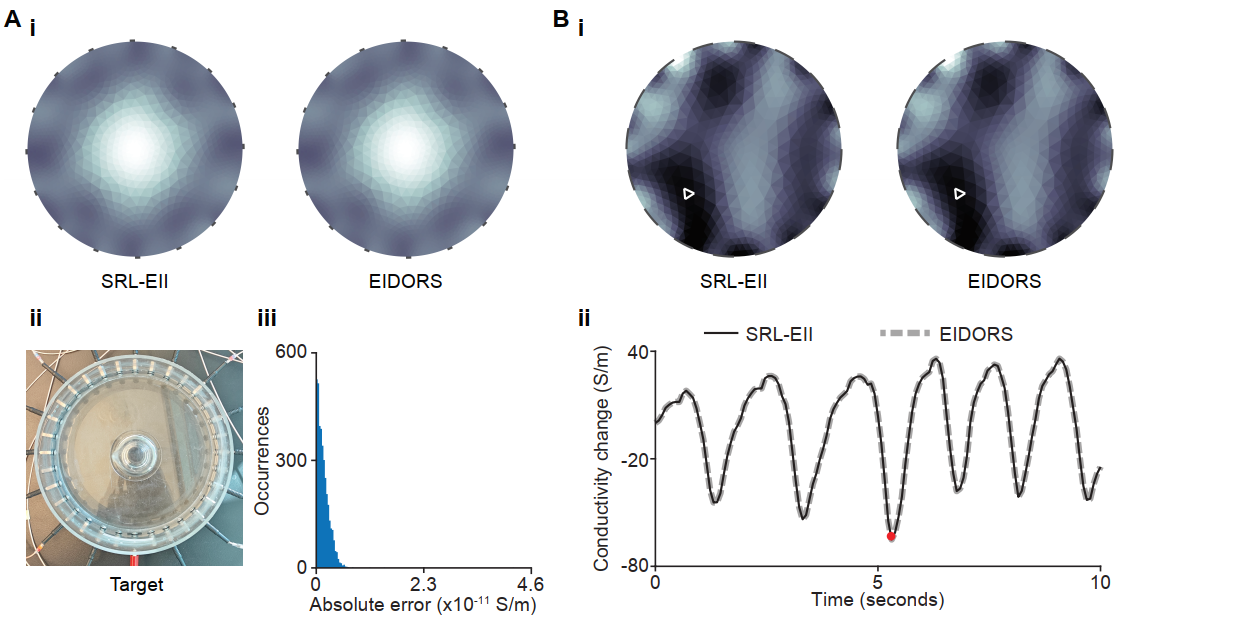

Electrical Impedance Imaging (EII) continues to redefine how we visualize physiological processes in real time. In a recent study titled “A Modular and Efficient Numerical Solver for Electrical Impedance Imaging,” presented at the 2025 IEEE International Symposium on Biomedical Imaging, researchers introduced the SRL-EII solver, an innovative and modular algorithm designed to tackle the challenges of EII reconstruction.

The study was validated through experimental data using the Sciospec EIT32 impedance tomography system, demonstrating a powerful synergy between computational modeling and real-world measurement accuracy. This article explores the solver’s key innovations and how advanced measurement solutions enabled high-fidelity imaging in both research and potential clinical applications. At the core of this success is Sciospec’s scalable, high-precision measurement technology.

Electrical impedance imaging is a powerful radiation-free imaging method with the potential to transform areas like lung ventilation monitoring. However, it comes with a unique computational challenge: the inverse problem of estimating internal conductivity from surface voltage measurements is nonlinear ill-posed, and highly sensitive to noise.

The SRL-EII solver is a modular and efficient numerical algorithm designed to address the inverse problem in Electrical Impedance Imaging. It aims to improve the speed and flexibility of image reconstruction, facilitating real-time imaging applications.

The SRL-EII solver introduces a modular approach to the reconstruction process, allowing for better isolation and management of different computational steps. This modularity enhances flexibility and can lead to faster and more accurate image reconstructions compared to traditional methods.

The SRL-EII solver represents a major step forward in real-time image reconstruction and it’s made possible by the precision and performance of Sciospec’s EIT32. This collaboration between advanced algorithms and high-quality measurement systems underscores the power of integrated innovation in medical imaging.